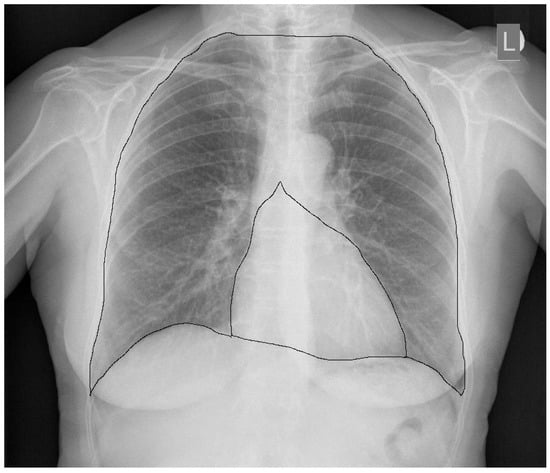

4. CTR as a Prognostic Factor